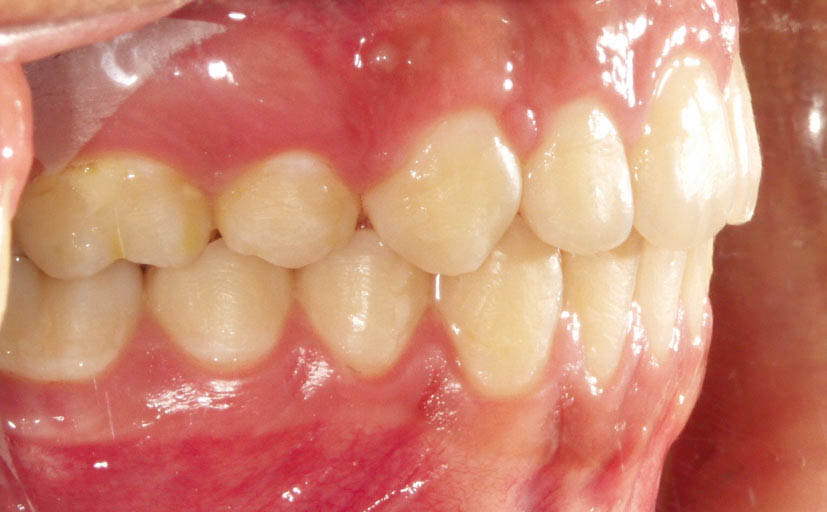

شکل 105-2: اکلوژن یک کاسپ کامل کلاسII

شکل 106-2: نتیجه درمان یک کاسپ کامل کلاسII تمام میشود.